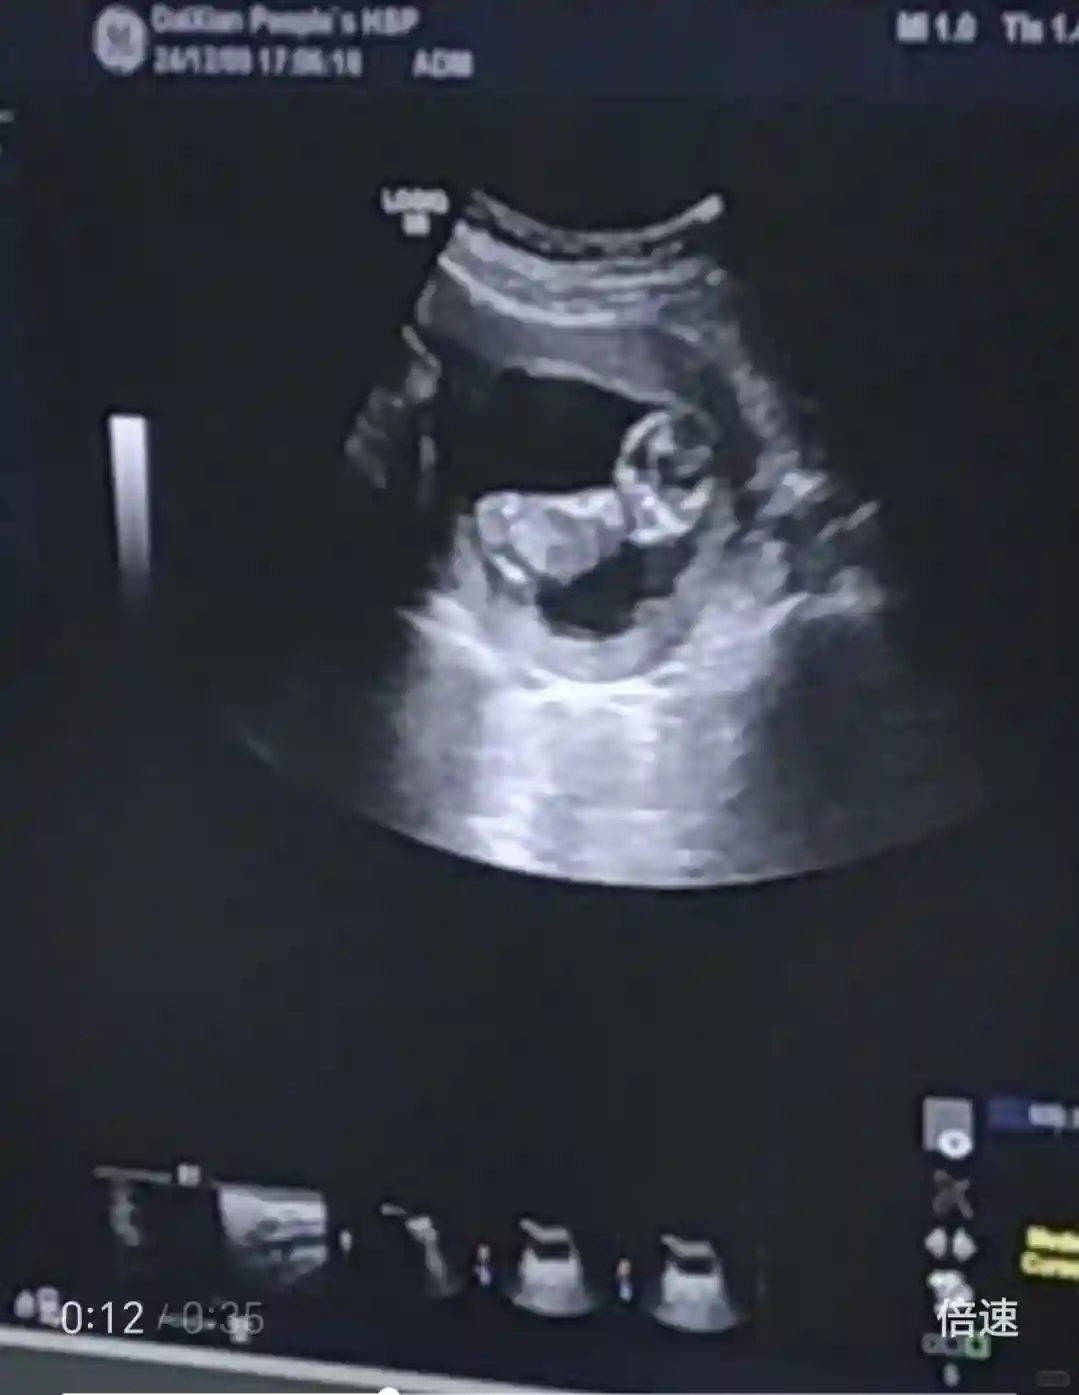

12周,我们做nt啦

图一是别人家nt,图二是我的nt崽子不配合,一直趴着,做了好几次

给其他姐妹一个建议,nt最好到大医院或者私立医院做,我为方便选择了离家近的县城医院,下午去的,排队做b超的人很多,到我的时候就快5点了,再加上崽子不配合(脉动、巧克力都吃了),到5点半又做了第二次。第二次一开始躺着,那个探头一碰到肚子又趴了,医生为赶着下班,就说透明层看起来并不厚,大致给估了一个数。我觉得如果在大医院总得多次调整看仔细了才会下结论吧,12周以后的检查果断去太原